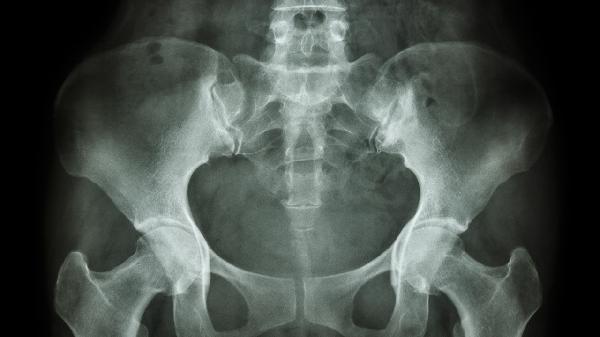

恥骨骨折一般不建議蹲著大便,可能加重疼痛或影響骨折愈合。恥骨骨折多由外傷、骨質疏松等因素引起,需根據(jù)骨折程度采取不同處理措施。

恥骨骨折后局部穩(wěn)定性下降,蹲姿會牽拉骨盆周圍肌肉韌帶,增加骨折端移位風險。坐便器可減少髖關節(jié)屈曲角度,降低對恥骨聯(lián)合的剪切力。急性期排便建議使用坐便椅或增高坐墊,保持脊柱直立、雙膝略高于髖部。若必須蹲便,需佩戴骨盆固定帶并由他人攙扶,避免單側用力。

部分穩(wěn)定性骨折患者經4-6周骨痂形成后,在醫(yī)生評估允許下可嘗試緩慢蹲便。但需注意動作輕柔,借助扶手分散壓力,出現(xiàn)疼痛加劇需立即停止。合并尿道損傷或嚴重移位骨折者絕對禁止蹲便,可能造成二次傷害。

恥骨骨折恢復期間應保持大便通暢,多攝入高纖維食物如燕麥、西藍花預防便秘。排便困難時可短期使用乳果糖口服溶液等緩瀉劑,但需避免長期依賴。定期復查X線觀察愈合情況,逐步在康復師指導下進行骨盆穩(wěn)定性訓練。